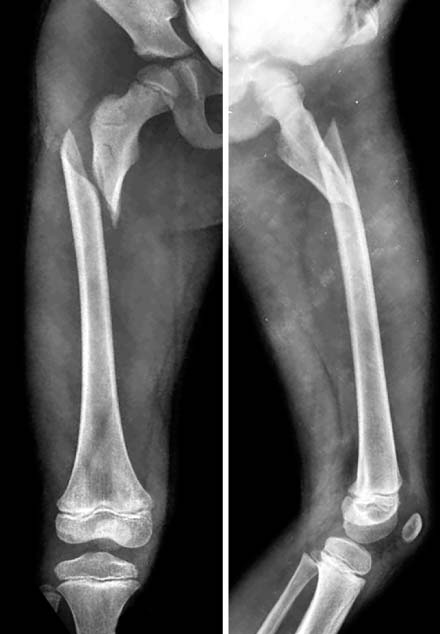

Fig. 9

In postoperative films (left), a good alignment was achieved. The fracture united at 3 months postoperatively (right).